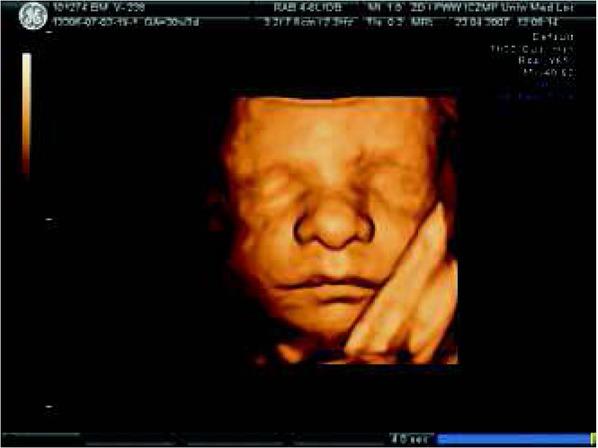

Fig. 3